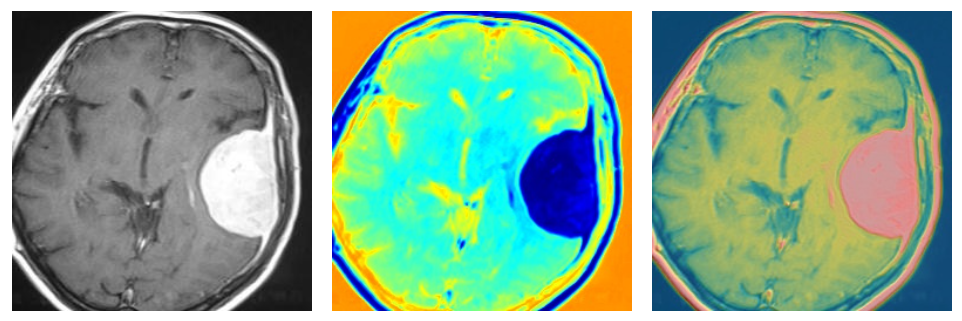

June 20, 2024

Brain Tumor Detection

View Project 🧑💻